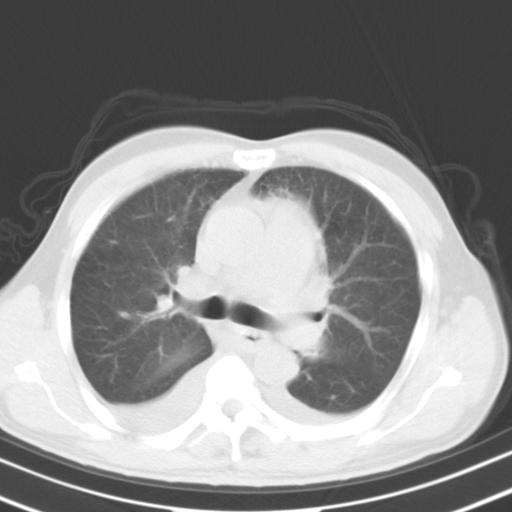

以下是引用zjzjr在2010-3-21 17:39:00的发言:[br]右下中心型肺癌并阻塞性肺炎/不张,纵膈淋巴结肿大,右侧大量胸腔积液,左侧少量胸腔积液

以下是引用zxl51642在2010-3-21 17:06:00的发言:[br]右下中心型肺癌并阻塞性肺炎/不张,纵膈淋巴结肿大,右侧大量胸腔积液,左侧少量胸腔积液,少量腹水。建议纤维支气管镜进一步检查。